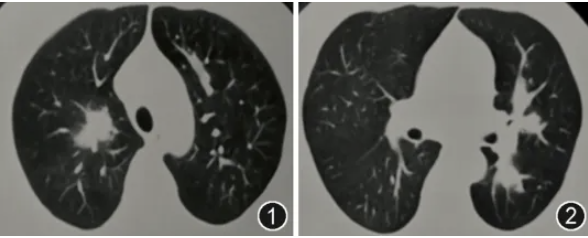

患者男,46岁,主因“咳嗽、咳痰伴发热27 d”于2025年1月27日入院。患者27 d前无明显诱因出现咳嗽、咳少量白黏痰伴发热,体温最高38.6 ℃。当地医院查血甲流IgM(+),胸部CT示双肺斑片影(图1,2),给予口服奥司他韦抗甲流、头孢菌素联合左氧氟沙星抗细菌治疗10 d后,复查胸部CT示双肺多发实变影伴空洞形成(图3,4),经验性加用伏立康唑抗真菌治疗1周后复查胸部CT示病变仍进展(图5,6)。既往史:2型糖尿病8年,口服二甲双胍、阿卡波糖、皮下注射甘精胰岛素治疗,未规律监测血糖;高血压1年,血压最高达170/100 mmHg(1 mmHg=0.133 kPa),未治疗及监测血压。无烟酒嗜好,否认过敏史,家族史无特殊。

图3,4 2025年1月14日(经抗甲流+抗细菌治疗10 d后)胸部CT示双肺多发实变影伴空洞形成

图5,6 2025年1月27日(经验性伏立康唑治疗7 d后)胸部CT示双肺多发实变伴空洞影较前进展